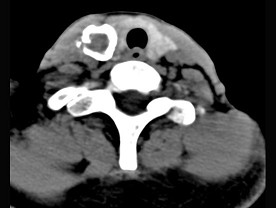

20.50歲女性患者,體檢發(fā)現(xiàn)右側(cè)甲狀腺有較硬結(jié)節(jié),CT掃描如圖所示,請(qǐng)選擇正確的描述和答案  (    )

正確答案:ABE